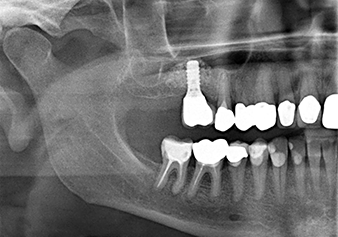

Для перемещения аугментационного материала в направлении верхнечелюстной пазухи атравматично, имплантат вводился очень медленно вручную (рис. 9). При этом мембрана еще раз выталкивалась в краниальном направлении. Через два месяца место операции зажило без раздражения. Через шесть месяцев рентгеновский контроль показал значительное увеличение помутнения, что свидетельствует об оссификации (рис. 10). Протезирование было проведено металлокерамической коронкой.